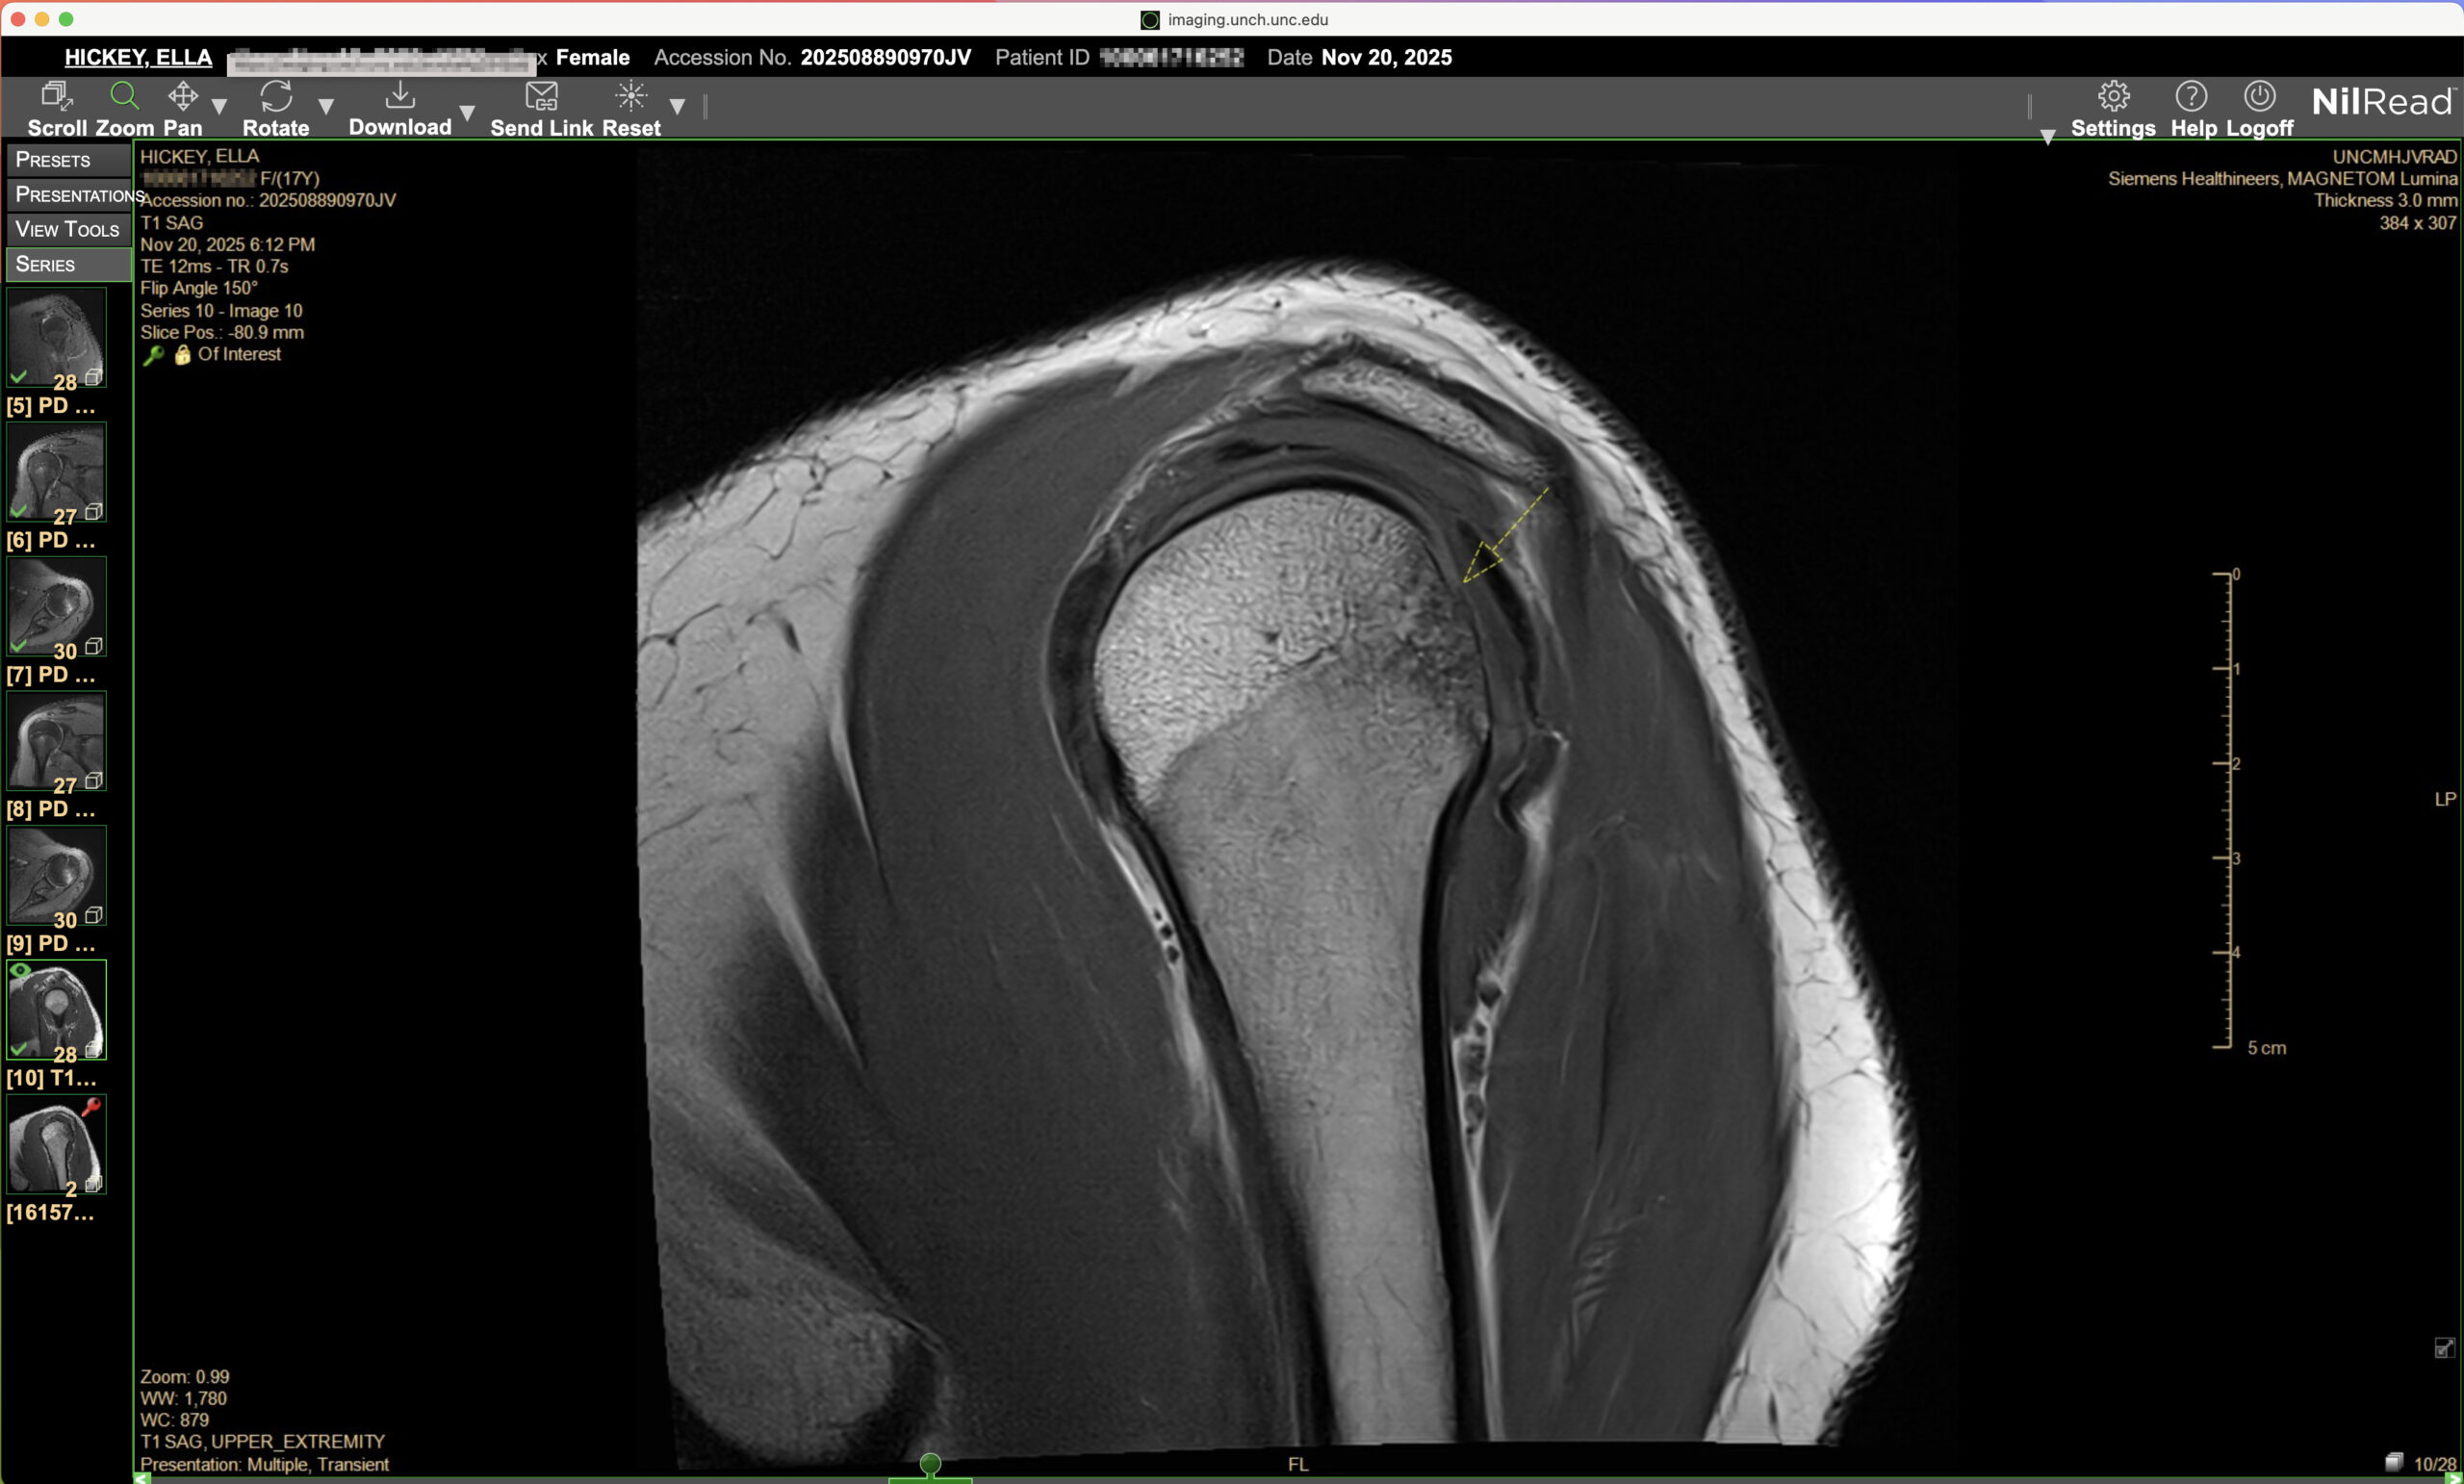

And because my body apparently doesn’t do anything small, it wasn’t just a dislocation. I had something called a Hill-Sachs lesion which is a fancy way of saying a chunk of bone got knocked out of place and my labrum was torn with the guys in the white coats call a Bankhart Lesion. I had to google what a labrum even was.